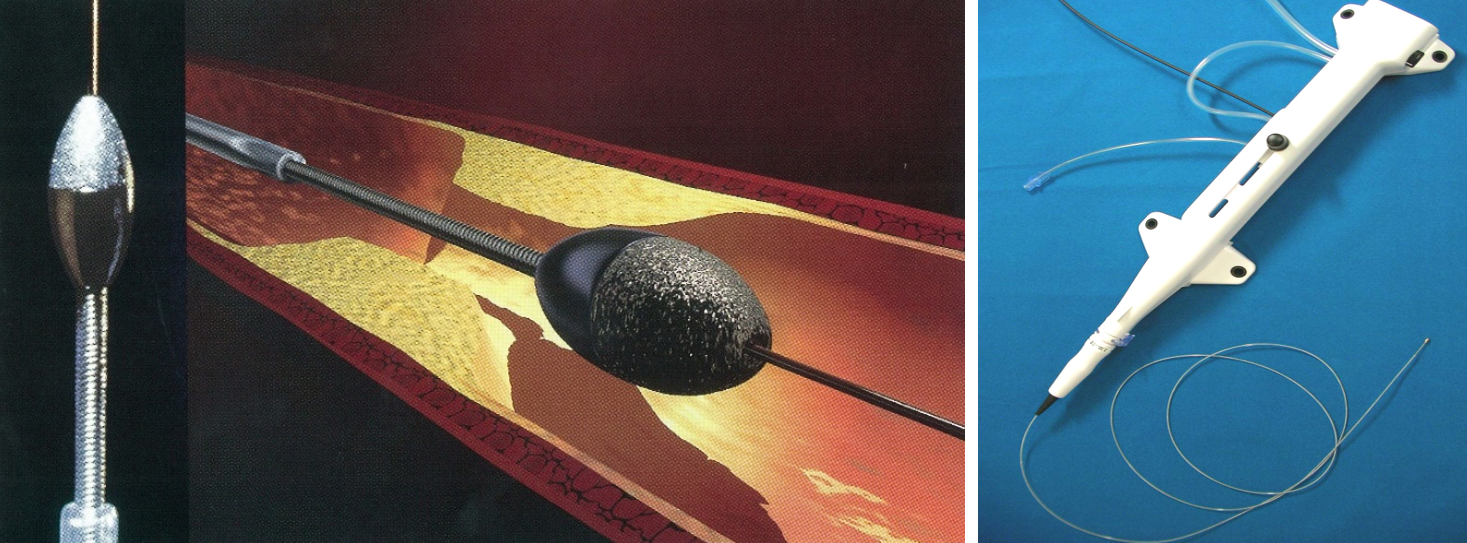

冠動脈インターベンション(カテーテルによる血管内治療)では、従来治療が困難であった高度石灰化病変に対する治療として、2020年より順次下記のデバイスを導入し、現在ほぼすべての冠動脈疾患に対するインターベンション治療が可能となっております。

ロータブレーター

ダイアモンドチップが散りばめられた、高速回転するドリルによって、前方の石灰化病変を削る治療です。削られた石灰化病変は赤血球よりも小さくなり、毛細血管をくぐりぬけて、最終的には脾臓で処理されます。これにより、その後バルーンやステントで治療可能となります。

ダイアモンドバック

ロータブレーターと同じくダイヤモンドチップのドリルですが、重心がカテーテルの中心より外側に偏位しており、高速回転の遠心力で側面の石灰化を削り取ります。ロータブレーターとは病変により使い分けます。

ショックウェーブ

もともと腎・尿管結石に使用されていた体外衝撃波治療を応用し、血管内でカテーテルを通じて衝撃波を発生することにより、石灰化を破砕してステントが十分拡張することが出来るようになります。治療に伴う合併症が極めて少ないという特徴があります。

Kereiakes DJ, et al. Principles of Intravascular Lithotripsy for Calcific Plaque Modification. JACC Cardiovasc Interv. 2021;14:1275–1292.より引用